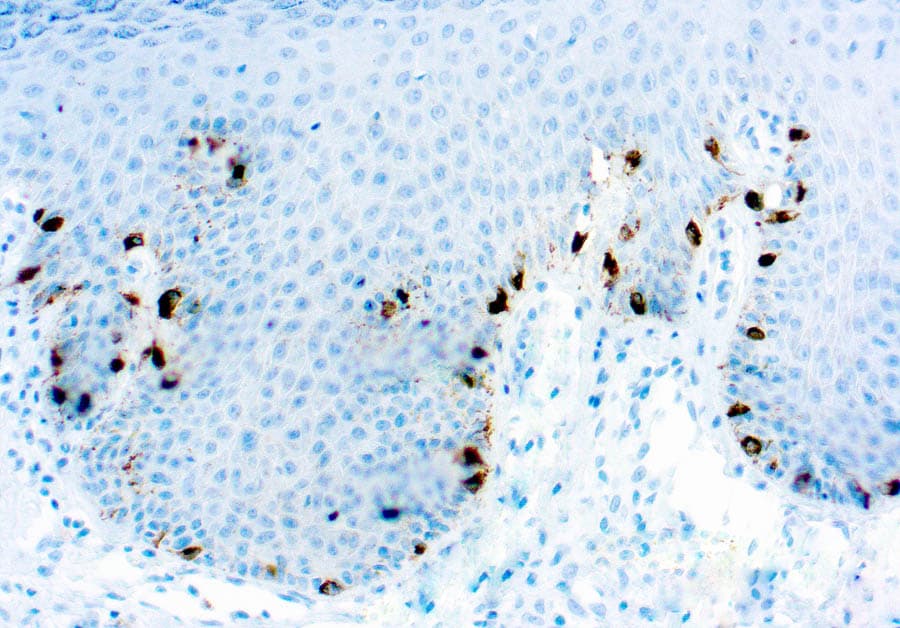

Melanoma section